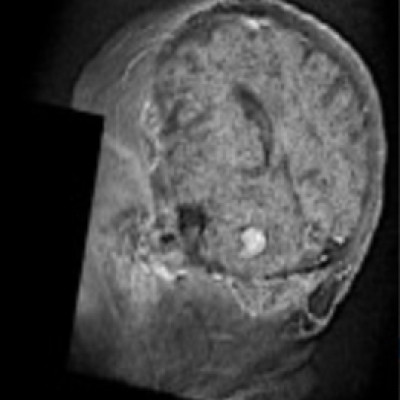

Brain metastasis (BM) is one of the main complications of many cancers, and the most frequent malignancy of the central nervous system. Imaging studies of BMs are routinely used for diagnosis of disease, treatment planning and follow-up. Artificial Intelligence (AI) has great potential to provide automated tools to assist in the management of disease. However, AI methods require large datasets for training and validation, and to date there have been just one publicly available imaging dataset of 156 BMs. This paper publishes 637 high-resolution imaging studies of 75 patients harboring 260 BM lesions, and their respective clinical data. It also includes semi-automatic segmentations of 593 BMs, including pre- and post-treatment T1-weighted cases, and a set of morphological and radiomic features for the cases segmented. This data-sharing initiative is expected to enable research into and performance evaluation of automatic BM detection, lesion segmentation, disease status evaluation and treatment planning methods for BMs, as well as the development and validation of predictive and prognostic tools with clinical applicability.